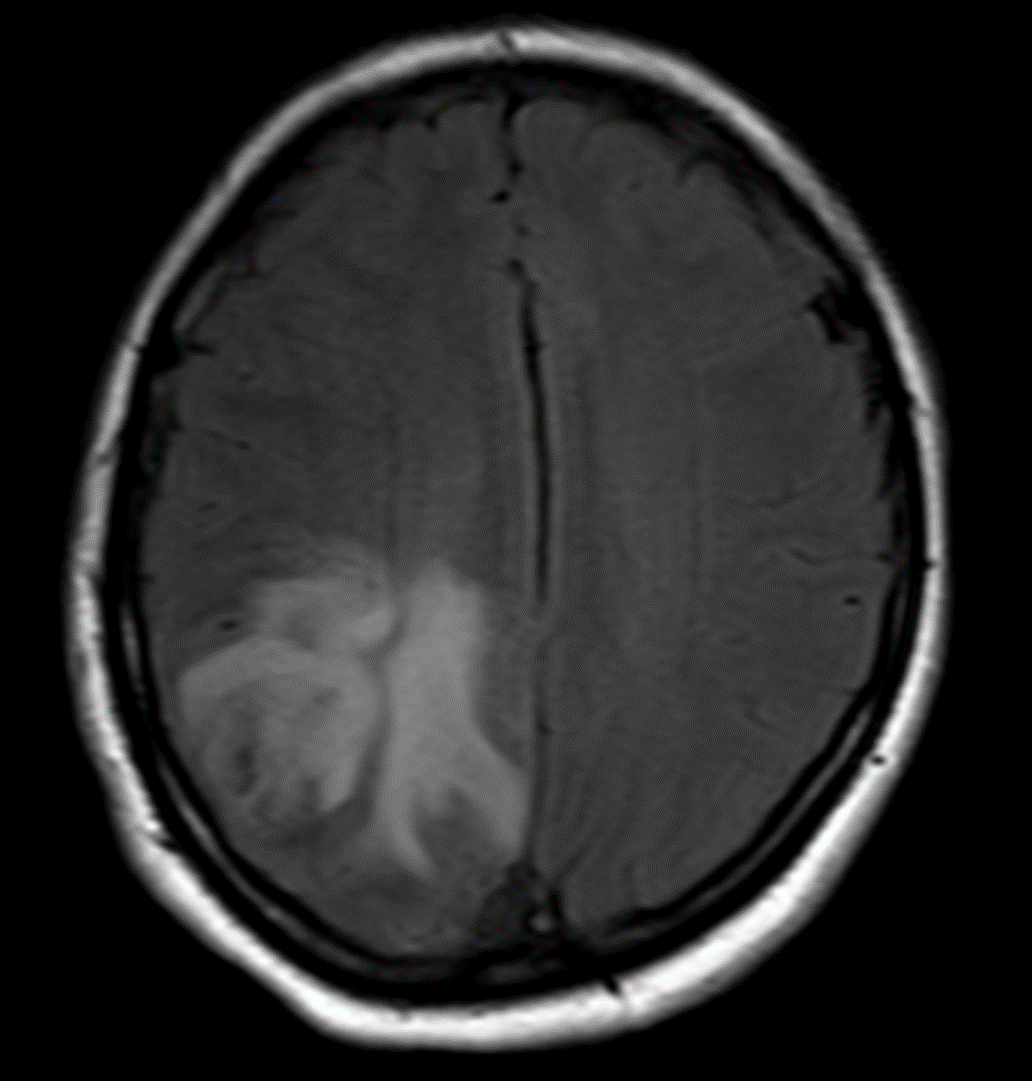

MRV shows left Transverse and sigmoid sinus thrombosis. No improvement after 2 days of IV heparin. Pt requires heavy sedation, ventilation for headache/agitation.

DSA also confirmed the extensive clot. In view of her recent LSCS 20 days ago, we were hesitant about giving IV lytics (urokinase infusion). Hence went in with an ACE 5 Max catheter and sucked out a mountain of clot